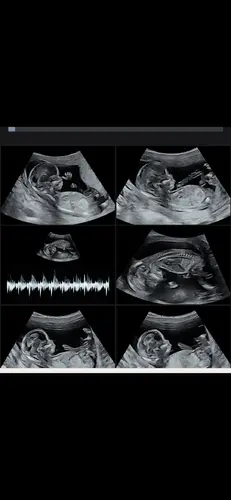

Wat denken jullie ?? 13 weken

Meisje!

🩷